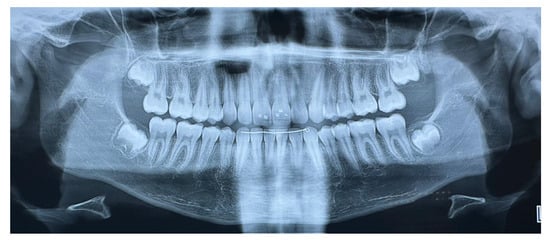

Extraoral clinical examination revealed a convex facial profile (Figure 2). Intraorally, the subject exhibited a Class II Division I type malocclusion with a bilateral Class II molar and canine relationship and an overjet of 9 mm. The maxillary incisors were proclined and, with the exception of a maxillary permanent canine, all permanent teeth were present in both arches, as shown in OPT (Figure 3).

Figure 3.

Orthopantomography at T0.